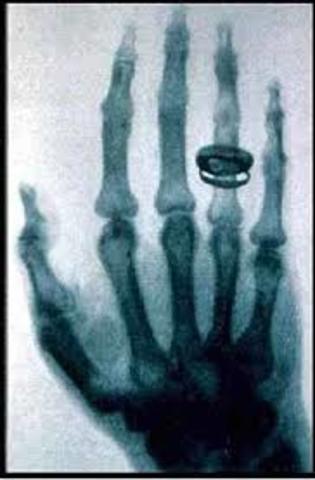

• Rayos X

Rayos X

Wilhelm Röntgen descubre los Rayos X, y logra observar los huesos de la mano.